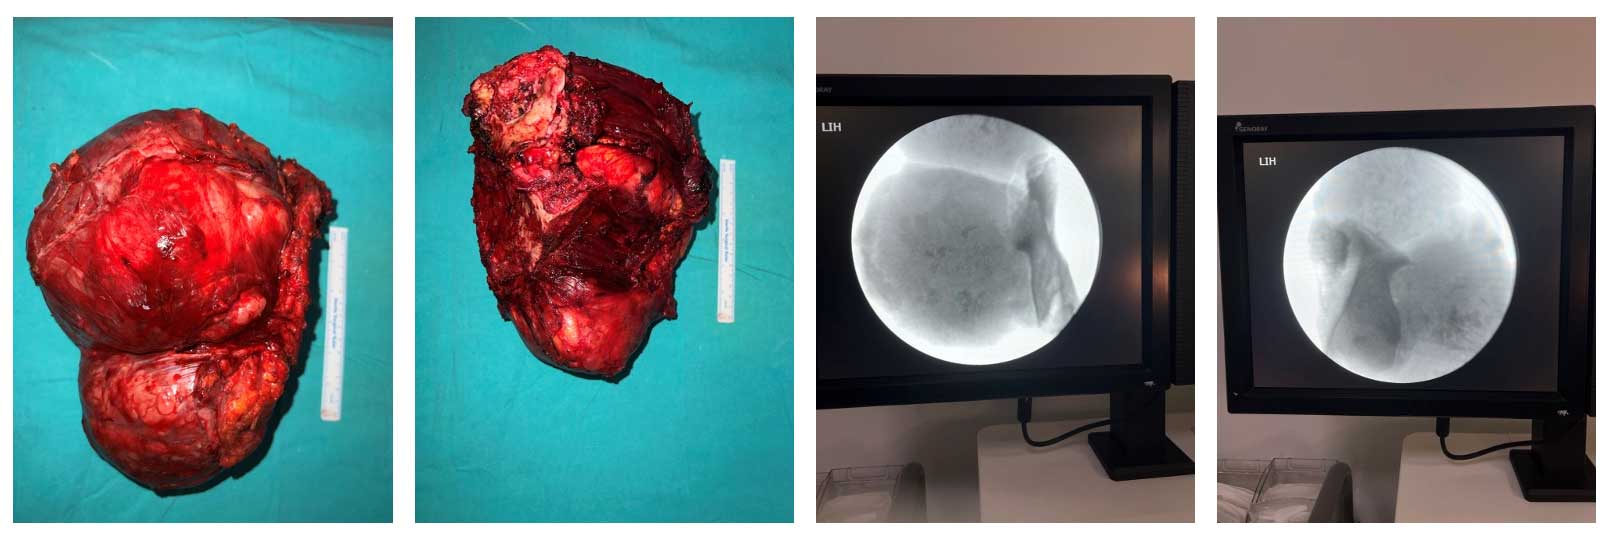

Ameliyat Esnası: Çıkarılan tümör dokusunun klinik ve radyolojik görüntüsü.